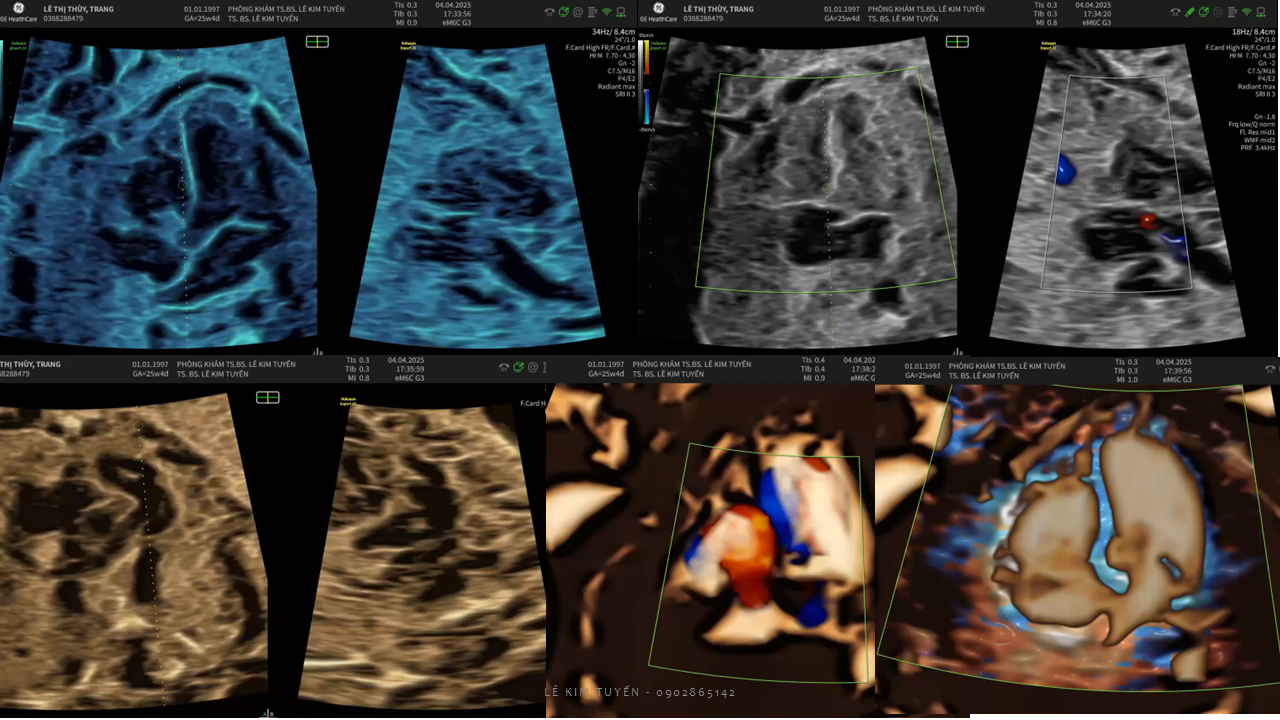

Siêu âm tim thai - Các kỹ thuật hiện đại

TS. BS. Lê Kim Tuyến